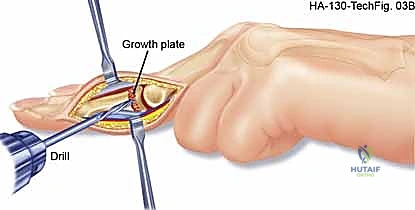

For glomus tumors, we plan a transungual or periungual approach depending on the exact subungual location mapped on MRI. The surgical field must be prepared for potential microsurgical reconstruction. Loupe magnification (minimum 3.5x) is mandatory for all cases, and an operating microscope should be on standby for digital artery repair or nerve neurolysis. The surgical template should utilize extensile incisions (Bruner zig-zag or mid-lateral) to allow broad exposure of the neurovascular bundles proximal and distal to the pathology, ensuring proximal control before entering the tumor bed.

For subungual glomus tumors, the approach requires precision to prevent nail deformity. A digital block is performed, and a finger tourniquet is applied. The nail plate is carefully elevated and removed (or partially removed) using a Freer elevator. The sterile matrix is incised longitudinally directly over the bluish hue of the tumor. The tumor, typically a 2-5 mm encapsulated, pearl-like structure, is gently shelled out using a curette or fine iris scissors. It is imperative to inspect the bony floor of the distal phalanx for erosions and curette any residual cells. The nail bed is then meticulously repaired using 6-0 or 7-0 absorbable sutures (e.g., chromic gut) under magnification. The native nail plate, if intact, is fenestrated and replaced as a biological splint, tucked under the eponychial fold to prevent synechiae.